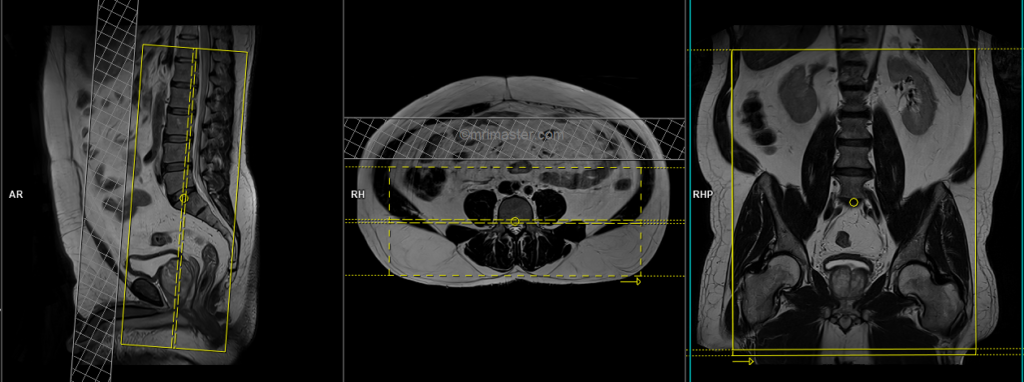

T2 tse sagittal 3mm

Plan the sagittal slices on the coronal plane and angle the planning block parallel to the spinal cord. Check the positioning block in the other two planes, ensuring an appropriate angle is given in the axial plane (parallel to the center of the vertebral body and the spinous process). Verify the position block in the sagittal plane; the field of view (FOV) must be big enough to cover the entire lumbosacral plexus from L1 down to the pubic symphysis (normally 350mm). Ensure that the slices are sufficient to cover the nerves from the right acetabulum to the left acetabulum. The phase direction should be head to feet to avoid motion artifacts from the abdomen.

Parameters

TR 4000-5000 | TE 100-120 | SLICE 3 MM | FLIP 130-150 | PHASE H>F | MATRIX 448X384 | FOV 350-350 | GAP 10% | NEX(AVRAGE) 2 |